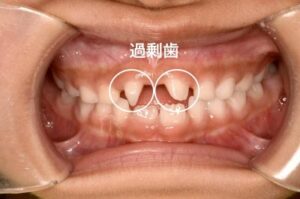

歯が多い「過剰歯」とは?

本来より多く歯ができる状態を、

歯科では過剰歯(かじょうし)と呼びます。

歯の芽(歯胚)が通常より多くできてしまうことで起こると考えられています。

過剰歯は珍しいの?

過剰歯そのものは、実はそこまで珍しくありません。

発生頻度はおよそ1〜3%程度といわれています。

100人いれば1〜3人程度にみられる計算です。

ただし、多くても1〜2本で、

今回のように10本以上の過剰歯があるケースは非常にまれです。